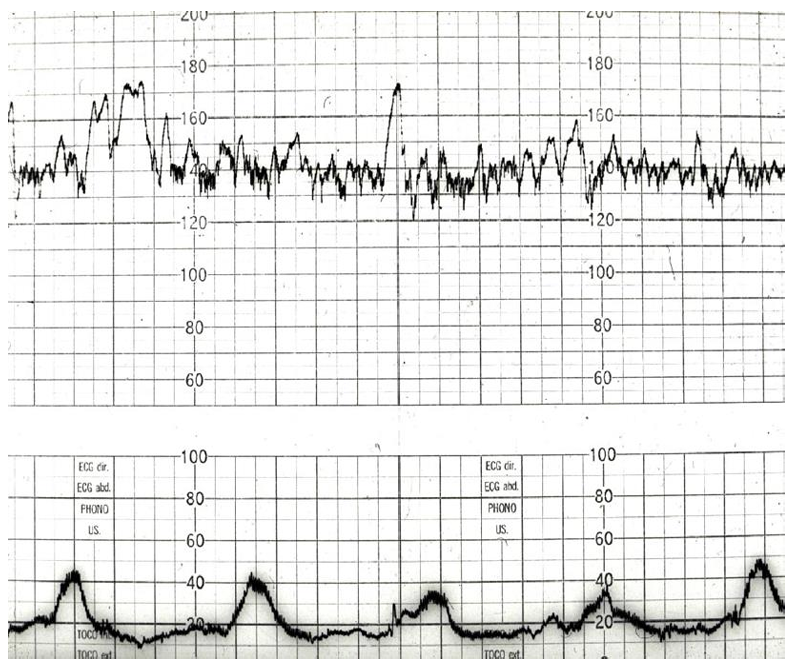

A cardiotocograph is performed (above), please interpret and provide summary (6 marks)